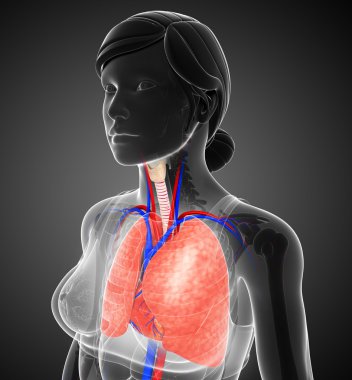

çizim, pulmoner dolaşım

ArkaplankişiİnsanKadınkanİlaçSolunumAvrupa DiliKardiyolojikalpdüzresim çalışmasıAkciğerSistemkemergemiüstünvenanatomiNormalauricletedavülarterAzalanyükselenCavaaortvena cavatorasikaşağıPulmonerventrikül20 30 yıldüz arka planKan damarıSolunum SistemiKan dolaşımıPnömolojiaortik kemerinen aortPulmoner dolaşımtorasik aortyükselen aortaPulmoner arterBenzer İçerikler